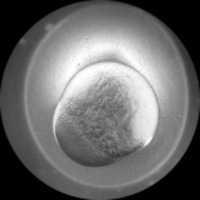

Research & Development: Researchers studying embryo development can use the AliDatabase to automate the process of identifying different stages of zeb1 cells. This can speed up research and reduce the possibility of human error in stage classification.

Medical Diagnosis: In fertility clinics or other medical settings, the AliDatabase can be utilized to identify and sort unfertilized or unhealthy zeb1 cells. This could help in diagnosing certain fertility issues and developing treatment plans.

Educational Tools: The model can be used as an educational tool for biology or medical students. By using AliDatabase, students can better understand the stages of zeb1 cell development and engage with interactive studying methods.

Pharmaceutical Testing: Companies developing drugs or treatments that impact cell growth could use AliDatabase to monitor how zeb1 cells respond at different stages to these drugs, aiding in efficacy and safety tests.

Quality Control in Lab Conditions: The model can be used to identify 'bad' or 'advanced' stages of zeb1 cells, indicating contamination or other issues in lab conditions, thereby assuring the quality of scientific experiments.